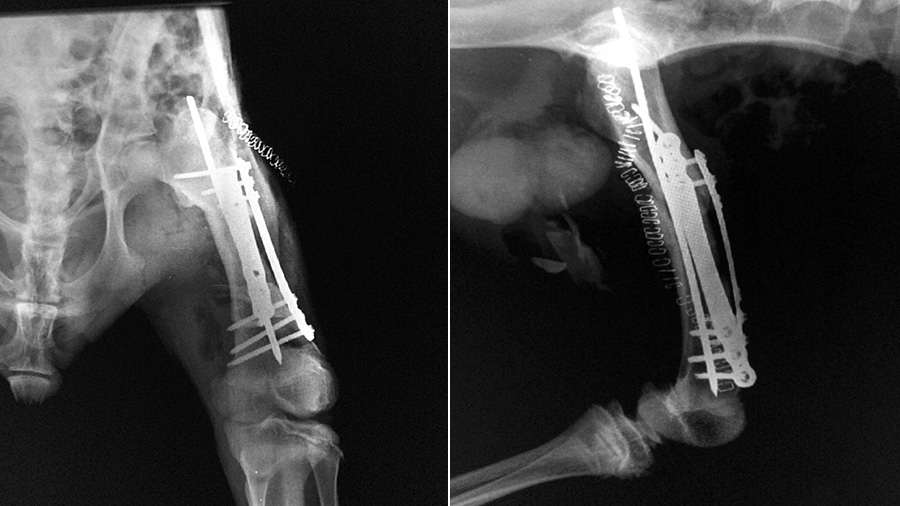

Using an intramedullary pin associated with double locking plates (rod and plate configuration) the fracture was bridged without an attempt to achieve perfect anatomic reduction but just focusing on the correct alignment.

“I had to identify similarities of anatomical structures. Some were different from what I was expecting. For example, the shape of the biceps femoris was deceiving and was converging toward what I expected to be the patella,” he said. “I discovered that the kangaroo doesn’t have a patella! I had to place the implant in a position that would not interfere with other anatomical structures, so I placed it as distally as I could. The realignment had to be perfect and the fixation super strong in order to allow the patient to bear weight on the hind limbs as soon as he was awake.”

Within a few weeks, the patient was at the safari park, once again proving the life-changing value of the AO principles.

“The end results were far, far more exciting than I expected. After the patient recovered, you couldn’t even tell which leg had been injured,” said Alessandro. “This case demonstrates that we can do something for these species by just applying the AO principles and using the best available implants for the particular fracture.”